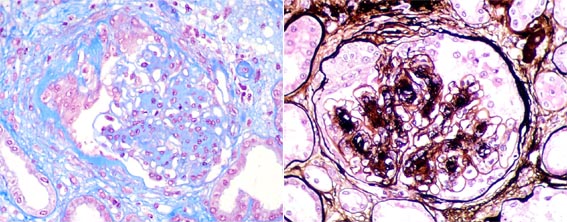

Figure 2.

First post-transplantation biopsy. Left: Masson's trichrome stain, X400;

right: methenamine silver stain, X400.

Figure 3.

First post-transplantation biopsy. Left: H&E, X400; right: PAS, X200.